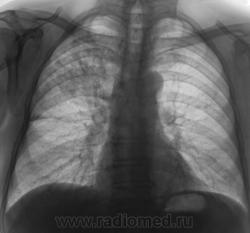

Пациент, при расшифровке флюорограмм, "взят на контроль". Произведено стандартное рентгенологическое исследование. Вот рентгенограмма.

По мне, так пневмония. Пролечить, посмотреть динамику.

Был нетак давно похожий случай, так же постродал S3,  в связи с локолизацией и консультацией заведующей отправил больного КТД (крайтубдиспансер), там пролечили антибиотиками и отправили домой,  на контроле всё чисто.

Добрый вечер, Валентин Львович. Жалоб нет, или не предъявляет. При туберкулезе - и инфильтрация, и распад, и т.д., а они не предъявляют - тогда ТБС.

По моему S2.

Да ведь у S3 граница по междолевой.